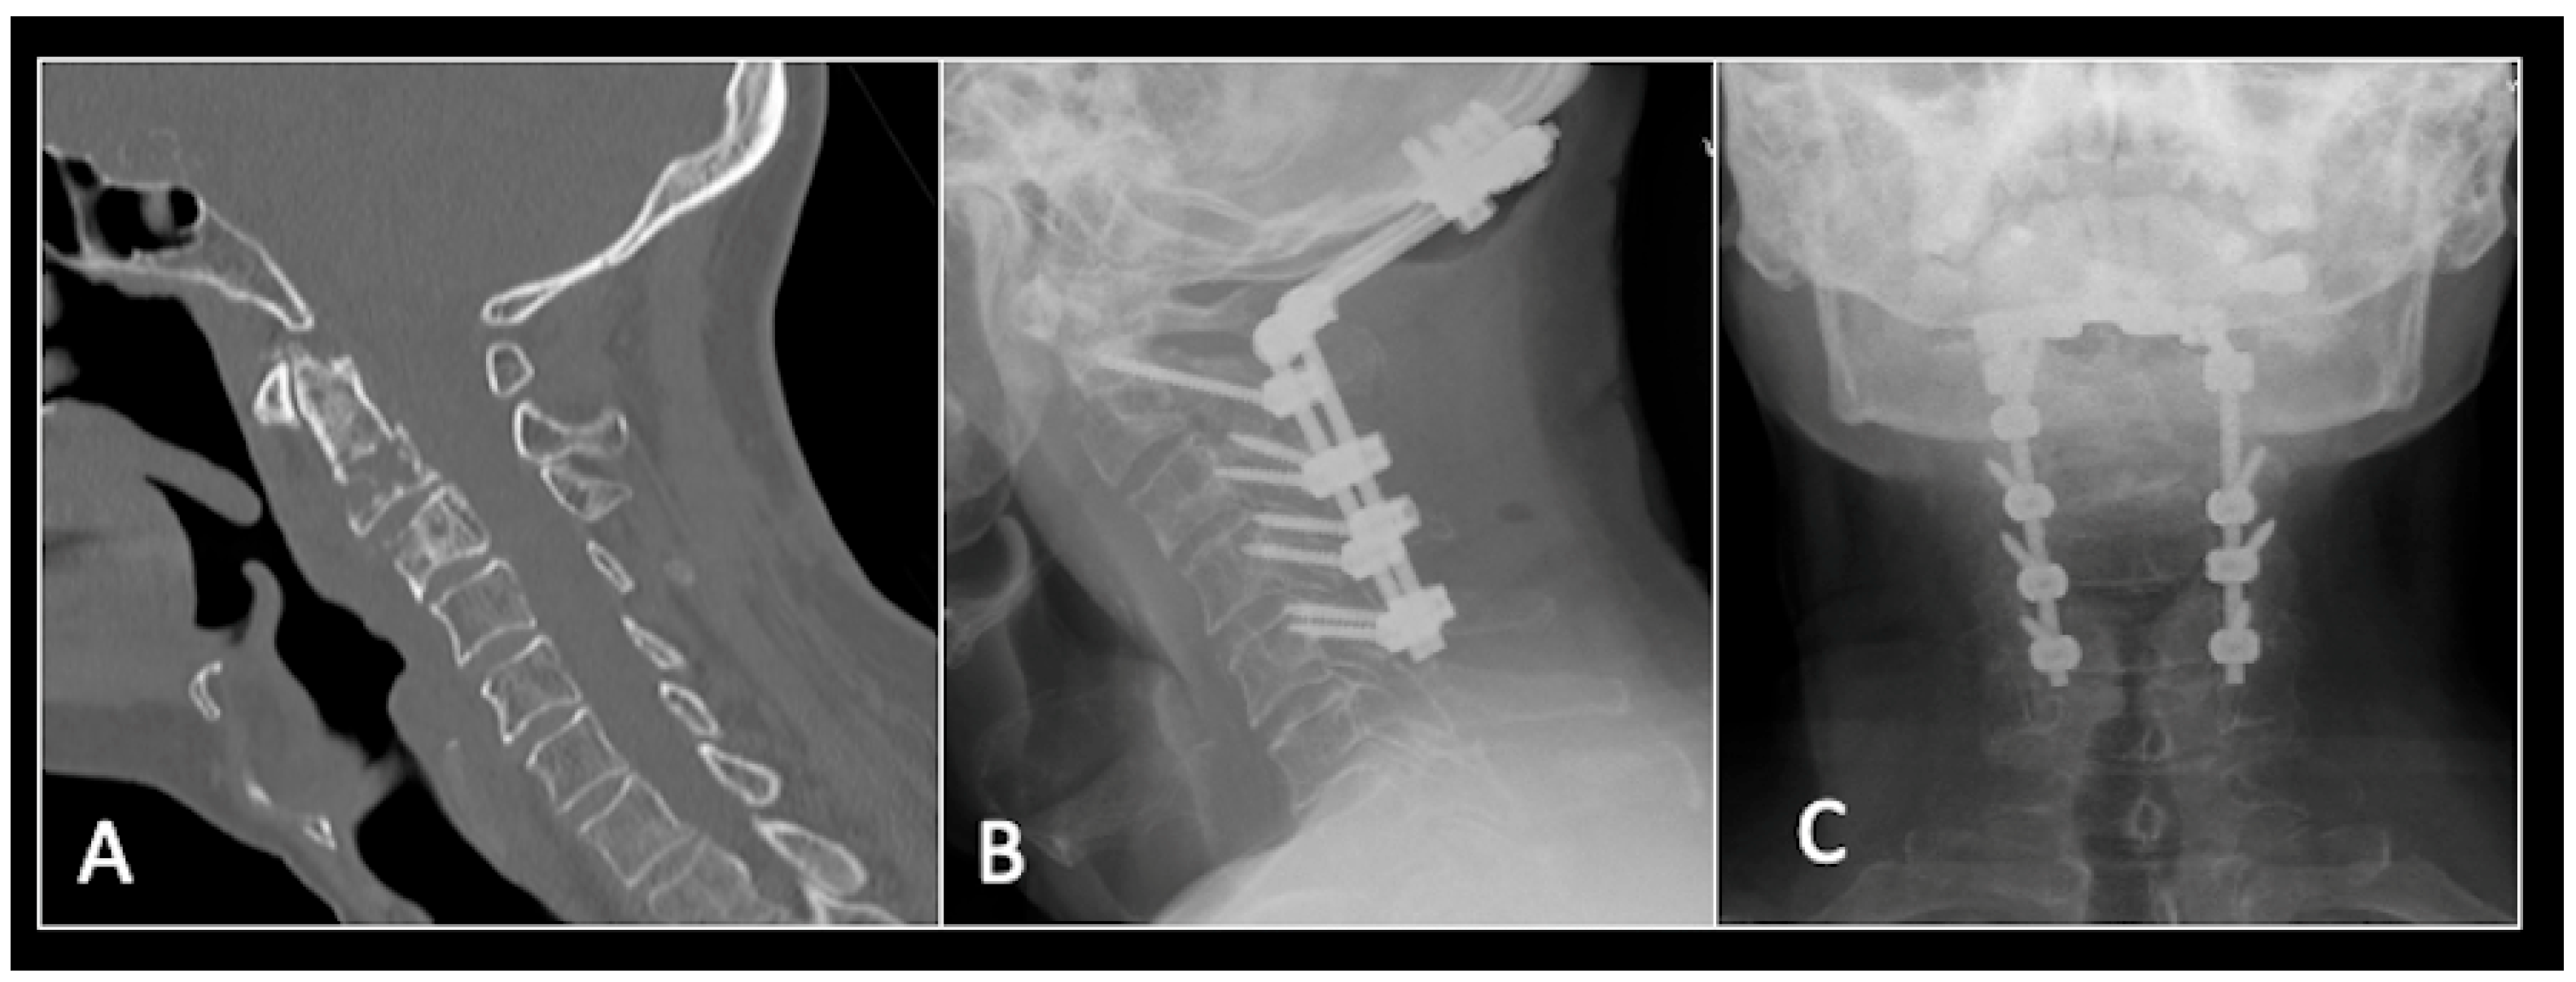

This 68-year-old male was referred to our institution with a 4 cm cervical mass localised to C2/3 following investigations for left-ear congestion and altered hearing (Figure 7). A CT-guided biopsy confirmed a conventional chordoma. The patient underwent separation surgery with adjuvant proton beam therapy. There was no evidence of disease progression on 3-monthly surveillance imaging (Figure 8). Approximately 12 months following separation surgery, the patient presented with acute onset neck pain. A C2 odontoid peg fracture was diagnosed requiring a posterior occipitocervical stabilisation procedure (Figure 9). Pre-stabilisation MRI imaging confirmed no tumour progression (Figure 10).

Figure 7.

The MRI demonstrates a left-sided lobular mass (arrow) with invasion of the C2/3 vertebral body and epidural extension, but no cord compression. The yellow line on the axial image indicates the axial slice level. (A) T2W sagittal; (B) T1W sagittal; (C) T2W axial.